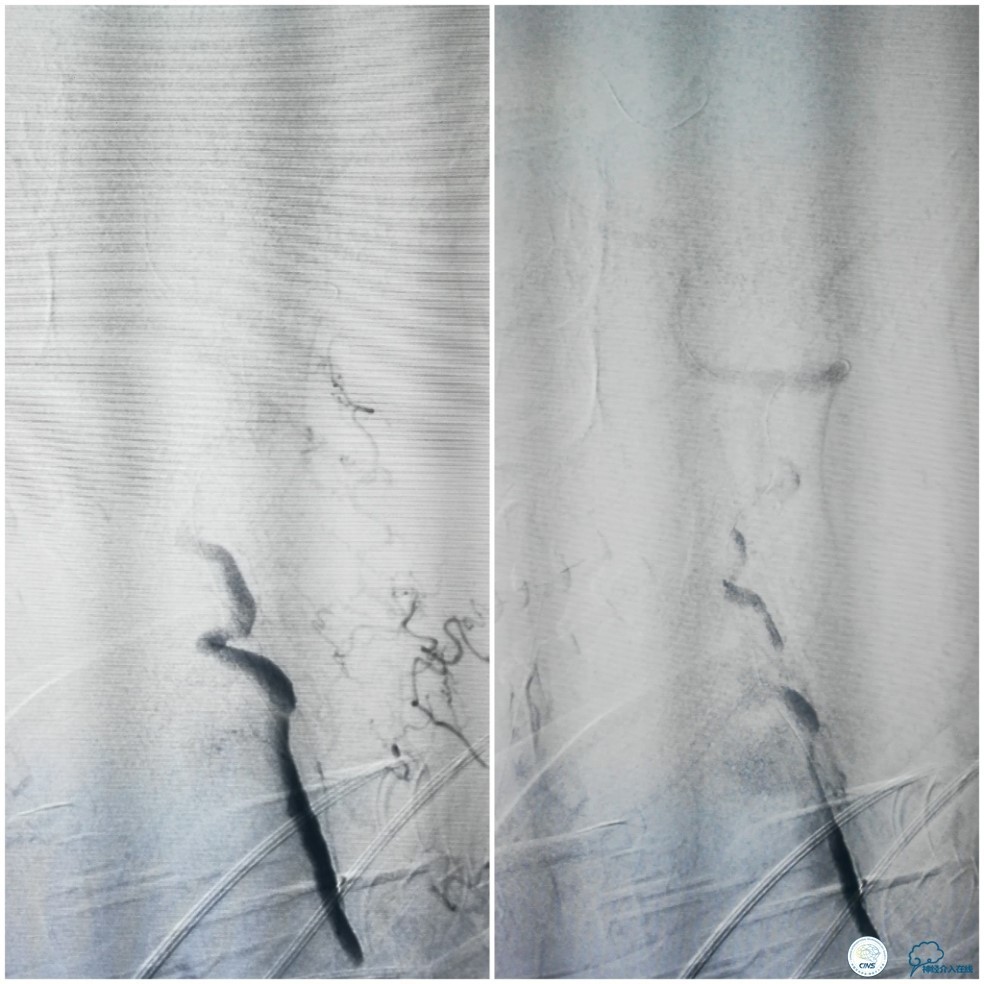

2. 避免重复路图,因为微导丝一旦到达着陆区后,迂曲血管被拉直会导致前向血流进一步减慢甚至停滞(图11系本例扩张后造影),这会给后续球囊或者支架的定位造成巨大困难。

图11